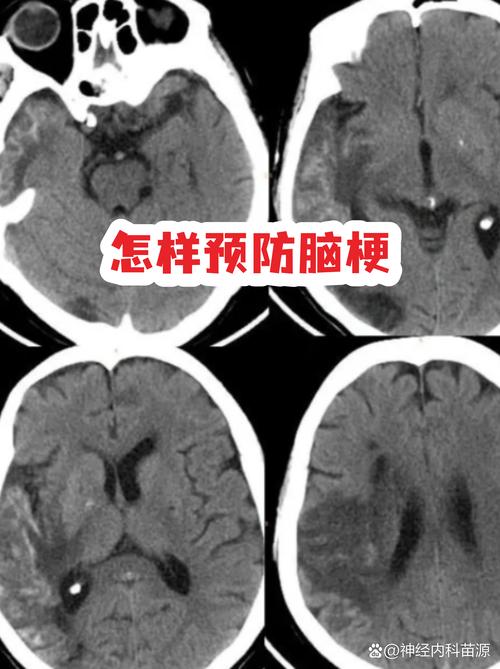

(图片来源网络,侵删)